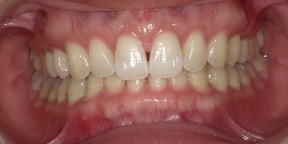

34歳女性のビフォーアフター

| 診断 | 叢生(デコボコがある状態)、開咬、下顎前突 |

| 治療方針 | インビザラインシステムにて主にIPR(歯と歯の間をわずかに削合してスペースを獲得する方法)を組み込んだ動的矯正治療を行った叢生改善と、開咬の改善のため臼歯部圧下をメインとした動的治療を行い、保定を行う。 |

| 治療費 ※ | 99万7千円(診断、型取り、PMTC、保定装置を含む料金) |

| 治療期間 | 3年5か月 |

| リスク | 1日20時間以上マウスピースを使用できない場合、歯が動かない可能性がある。装着時や食事時に痛みを伴う。歯肉退縮や虫歯になるおそれがある。また、指導通りに装着できていない場合や適切なブラッシングが出来ていないとそのリスクが高くなる。歯根が短くなることがある。ごくまれに歯の神経が損傷してしまうことがある。過去にぶつけたり深い虫歯治療をしたことがあるとそのリスクはやや高くなる。矯正後には保定装置が必要。適切な使用ができない場合、後戻りの原因となる。将来的に歯並びが動いて再矯正が必要な場合がある。舌癖が強い場合や正常に生えていない親知らずがある場合、その可能性が高くなる。 |